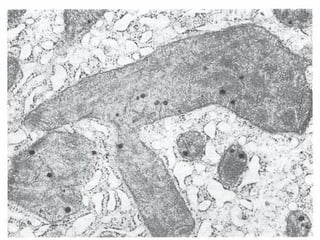

Funky mitochondria

• Mitochondrial swelling with formation of

large amorphous densities in matrix

• Ultrastructural changes

– Breaks in cellular and organellar membranes

– Larger amorphous densities in mitochondria